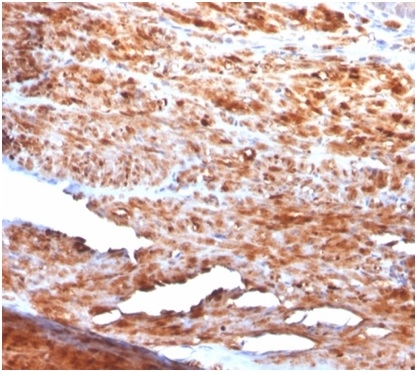

IHC analysis of formalin-fixed, paraffin-embedded human uterus. Stained using Desmin antibody (rDES/1711) at 2ug/ml in PBS for 30min RT. HIER: Tris/EDTA, pH9.0, 45min. Secondary: HRP-polymer, 30min. DAB, 5min.

Immunohistochemistry (Formalin-fixed): 1-2ug/ml for 30 minutes at RT. Staining of formalin-fixed tissues requires heating tissue sections in 10mM Tris with 1mM EDTA, pH 9.0, for 45 min at 95C followed by cooling at RT for 20 minutes